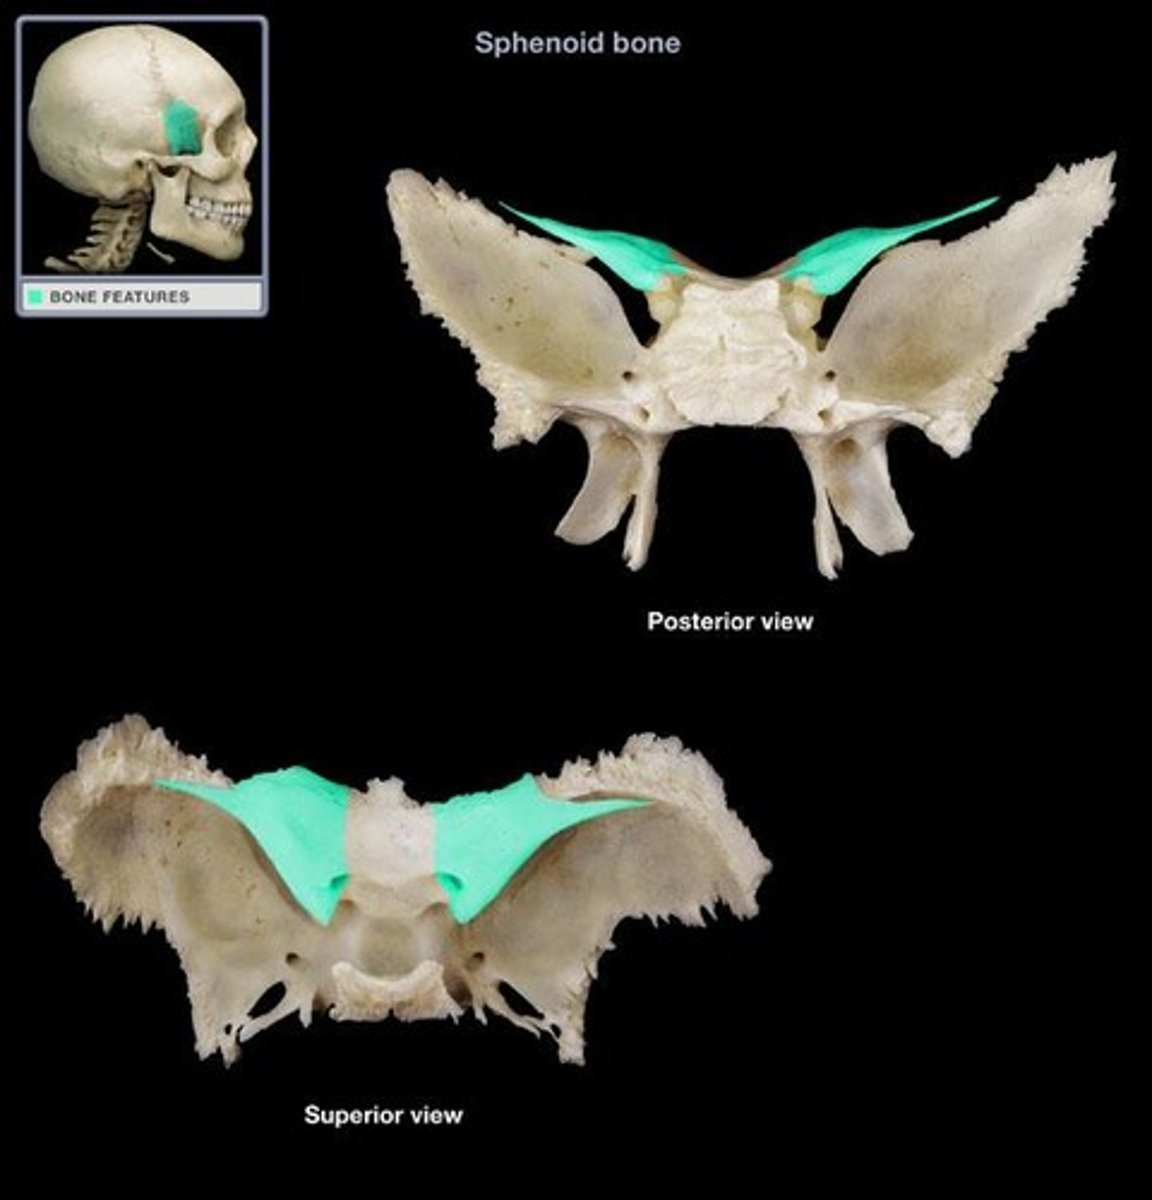

os sphenoidale

pleištakaulis

mašasis ir didysis sparnai

corpus

Pleištakaulio kūnas

ala major

Didysis sparnas

ala minor

mažasis sparnas